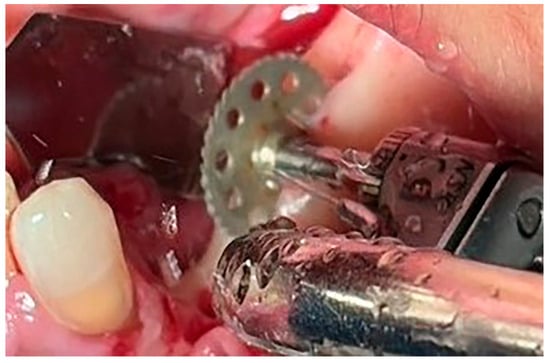

Figure 1. Bone measurement on a cross-sectional image—CBCT (Green X™ 12®, Vatech, Prague, Czechia).

Local anesthesia using 4% articaine with adrenaline 1:100,000 (Septanest®, Septodont, Saint-Maur-des-Fossés, France) was administered. After the midcrestal longitudinal incision, a full thickness mucoperiosteal flap without a vertical releasing incision was elevated and the top of the alveolar ridge was flattened to the width of 4 mm (Figure 3). Preparation of the implant bed was performed with only one twist drill from the set (Esset kit®, Osstem, Seoul, Republic of Korea) which corresponded to the implant length (Figure 4). Following the preparation of the implant bed with the twist drill, a midcrestal longitudinal osteotomy was performed with a special saw with the speed of 1200 rpm (Figure 5). A specially designed set of expanders (Esset kit®, Osstem, Seoul, Republic of Korea) was used gradually in order to separate the buccal plate from the lingual cortical plate, according to their elasticity (Figure 6A–C).